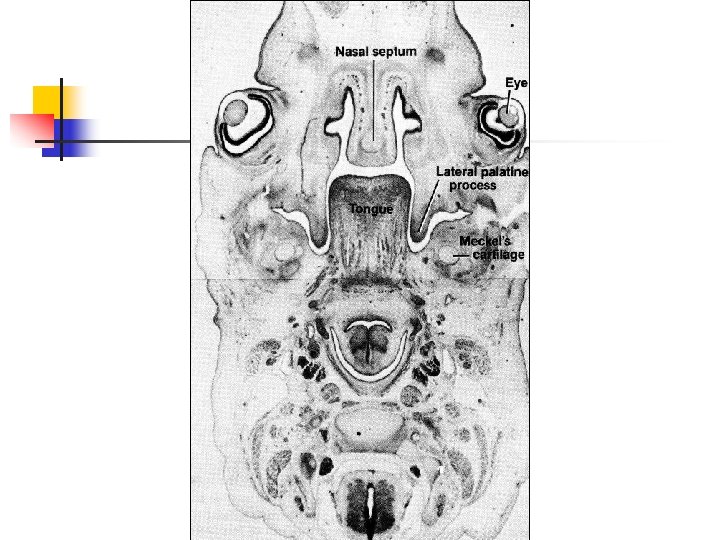

Развитие полости рта n Одна общая полость разделяется на три отдела в результате: n n роста носовой перегородки и формирования нёба

Формирование нёба n n Два боковых нёбных отростка (вторичное нёбо) Срединный нёбный отросток (первичное нёбо) В месте слияния всех отростков остается отверстие (резцовое)